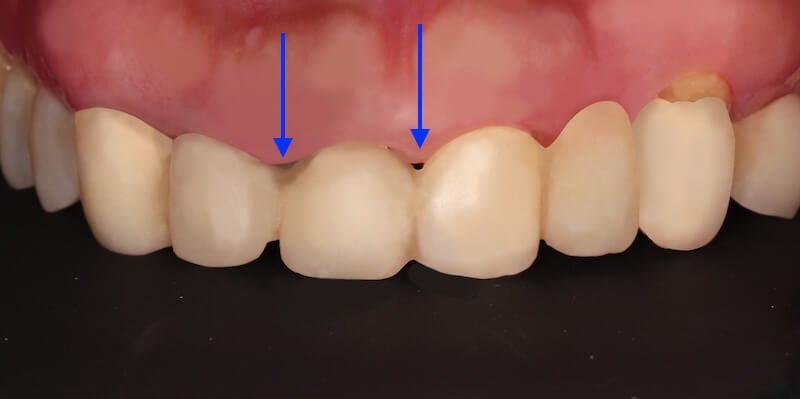

口內的檢查可以看到,在上顎前面六顆假牙,牙齦明顯腫起來。這可能來自兩個原因:

經過第一階段的療程後,我們持續追蹤 Ms.H 刷牙的情況,並且在大約兩個月後追蹤整體復原的進度,我們可以看到牙齦腫大的狀況明顯改善了許多,消腫以後產生了不少縫隙: